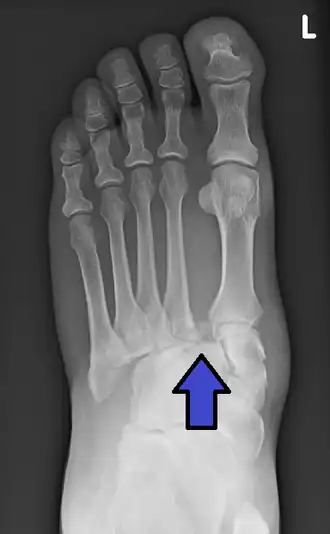

| Uma radiografia de uma lesão de Lisfranc, mostrando alargamento entre a base do 1.º e do 2.º metatarsiano. | |